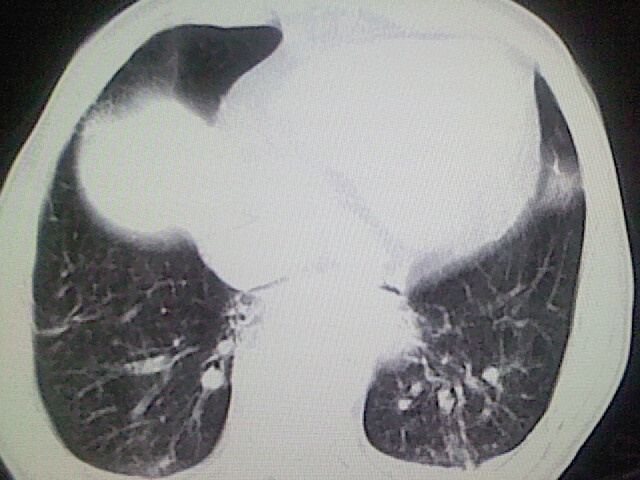

以下是引用zsl6918在2008-8-28 16:49:00的发言:[br]双肺炎性病灶,食管狭窄估计与心房增大压迫所致。

以下是引用xulianj在2008-8-28 20:36:00的发言:[br]慢支肺气肿伴感染,右上肺陈旧性结核;食道建议胃镜检查。

以下是引用wqs571018在2008-8-28 21:18:00的发言:[br]慢支继发感染,右上肺陈旧性结核;食道建议胃镜检查。